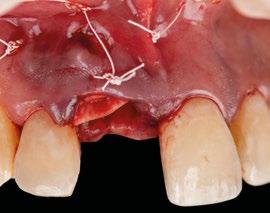

7.- Interponemos membrana reabsorbible entre tejido conectivo y alveolo. (Figuras 20 y 21)